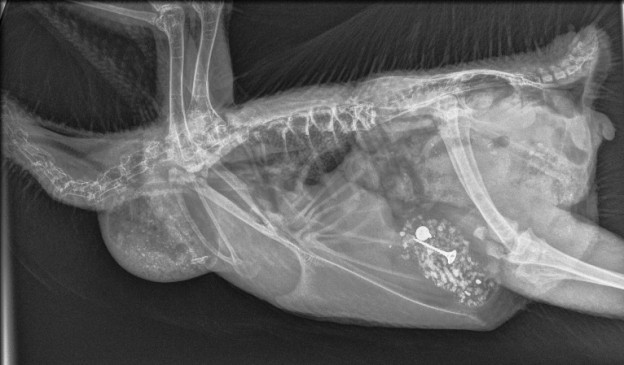

Metal Bits Inside Chicken (Bird Vet Melbourne)

The most effective diagnostic tool for finding ingested metal debris is x-rays of the gizzard and stomach. Of course, if foreign objects were found the recommendation would be to have them surgically removed. Many people, at that point, would opt to have their bird euthanized rather than spend a fair bit of money on an operation for a chicken.